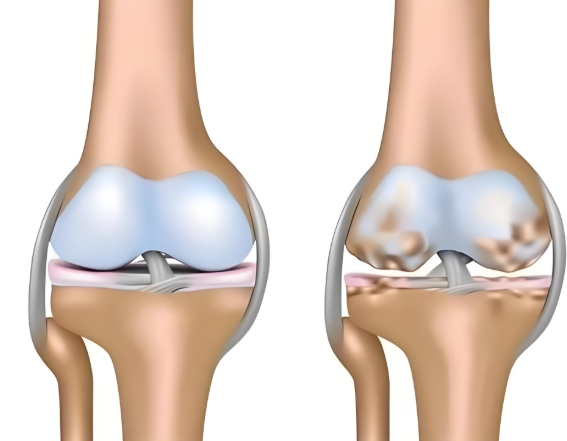

臨近年底,多地強(qiáng)降溫來襲,“老寒腿”又如期成了不少人的困擾。其實(shí),“老寒腿”并非單純的畏寒,而是骨關(guān)節(jié)炎的通俗叫法。寒冷只會誘發(fā)和加重關(guān)節(jié)疼痛、僵硬等不適,真正的患病根源是關(guān)節(jié)軟骨的磨損與退化。而氨基葡萄糖類藥物,就是直擊骨關(guān)節(jié)炎患病根源的臨床常用干預(yù)方案。不過,它還分鹽酸和硫酸氨基葡萄糖兩種,鹽酸和硫酸氨基葡萄糖的作用與功效差異在哪?該如何選對藥物、精準(zhǔn)護(hù)關(guān)節(jié)?

鹽酸和硫酸氨基葡萄糖膠囊都是氨基葡萄糖類藥物,能為關(guān)節(jié)軟骨提供合成原料,在促進(jìn)軟骨基質(zhì)的修復(fù)與再生的基礎(chǔ)上,補(bǔ)充關(guān)節(jié)滑液以減少摩擦,同時(shí)通過抑制關(guān)節(jié)腔內(nèi)的炎癥因子,從多個(gè)方面幫助延緩骨關(guān)節(jié)炎的進(jìn)展[1],但它們在臨床療效上卻存在一定差異。

根據(jù)國際醫(yī)學(xué)四大期刊之一《美國醫(yī)學(xué)會雜志》上發(fā)布的一項(xiàng)研究表明,硫酸氨基葡萄糖在緩解膝骨關(guān)節(jié)炎疼痛、改善關(guān)節(jié)活動(dòng)功能方面,效果優(yōu)于鹽酸氨糖等33種骨關(guān)節(jié)炎常用藥[2]。還有相關(guān)研究顯示,硫酸氨基葡萄糖不僅能延緩關(guān)節(jié)間隙變窄,還能從根源改善關(guān)節(jié)結(jié)構(gòu)、減緩磨損。而鹽酸氨基葡萄糖在這一關(guān)鍵指標(biāo)上的效果尚未明確。因此,在關(guān)節(jié)保護(hù)的“確切性”上,硫酸氨基葡萄糖顯然更具優(yōu)勢。

硫酸氨基葡萄糖膠囊中含有的硫酸根是人體關(guān)節(jié)軟骨中蛋白聚糖的天然組成成分。這種與人體兼容的“內(nèi)源性”特質(zhì),讓它口服后吸收利用率可達(dá)90%[3]。而且對胃腸道會更溫和,耐受性更佳。反觀鹽酸氨基葡萄糖膠囊,它所含的氯離子不是關(guān)節(jié)正常代謝所需,可能會在口服后刺激胃腸道黏膜[4]。這種刺激不僅會引起腸道不適,還會干擾藥物在腸道的吸收,降低其生物利用度。